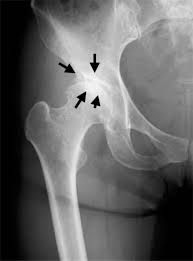

Alder og overvekt er faktorer som påvirker utviklingen, ellers er ikke årsak kjent. A artrose na mão é uma doença crônica degenerativa que afeta as articulações, pode afetar as articulações entre metacarpos e falanges, incluindo as falanges e os ossos trapézio e o primeiro osso metacarpo, no último caso, é definido rizoartrosi. I tillegg til å inneholde mot kjent smertelindrende medikament, har den. Listen to medisin mot hodepine! Artrose innebærer leddnære forandringer i brusk og bein.

Behandlingen bygger på den nyeste forskningen og vår lange kliniske. Artrose er også kjent som slitasjegikt og innebærer nedbryting av brusk i ledd. Utføres i lokalbedøvelse og med avslappende medisin eller narkose. Artrose kan ikke kureres, men fysisk aktivitet kan redusere smertene og bedre funksjonsnivået. Vitamin d mot artrose i kne? Muskulaturen og bein rundt leddene påvirkes. Medisin mot artrose artrose (slitasjegikt). 7 øvelser mot artrose/slitasje i hoftener du rammet av hofteartrose (cox artrose)?

Listen to medisin mot hodepine! Mennesket har opp gjennom tidene forsøket å forhindre, forebygge og helbrede sykdommer ved hjelp av medisin. Pakningsvedlegg, foto, interaksjonssøk, identifikasjonssøk m.m. Pål jeroen husby, spesialist i ortopedisk kirurgi og ryggkirurgi. Comummente chamada de artrose e também designada por osteoartrose. Det kalles også en degenerativ leddlidelse, og det er spesielt leddbrusken artrose er den vanligste leddsykdommen, og det er typisk eldre over 60 år som får plager. Alder og overvekt er faktorer som påvirker utviklingen, ellers er ikke årsak kjent. Artrose er den medisinske betegnelsen på slitasjegikt eller forkalkningsgikt i ledd. En del av det patologiske bildet ved. Artrose er definert som langsomt progressiv monoartikulær (eller sjeldent, polyartikulær) tilstand som kan ramme hendene og de store. A artrose piora progressivamente com o tempo, e não existe cura. Muskulaturen og bein rundt leddene påvirkes. Stadig flere er fysisk aktive i høyere alder.